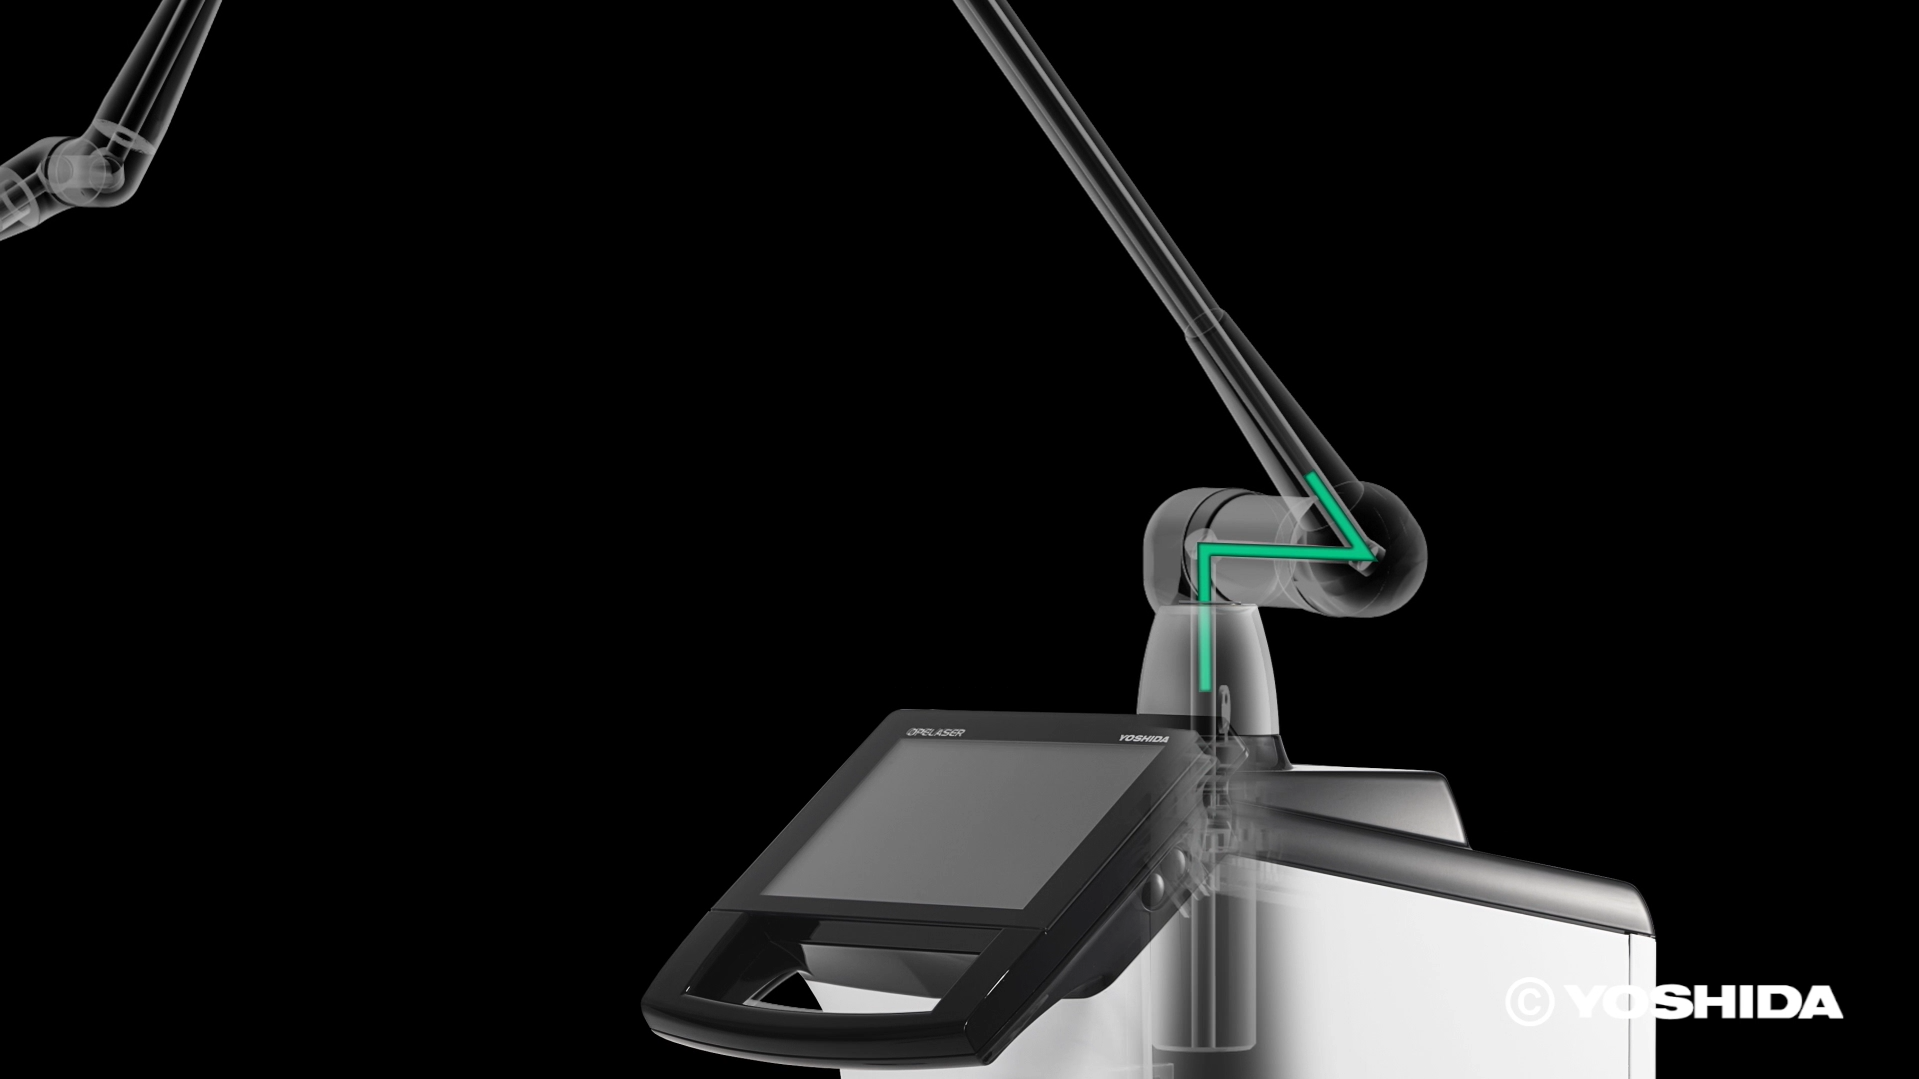

(1)オペレーザー商品とは、株式会社吉田製作所が製造する歯科用レーザー機器であって、「オペレーザー」を販売名に含む商品をいいます。